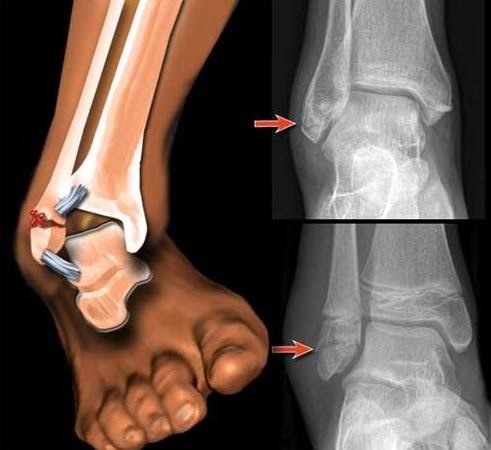

Сегодня хочу рассказать историю про реабилитацию. Ольга пришла ко мне 3 месяца назад. Диагноз — перелом лодыжки со смещением, 2 месяца в гипсе.

Гипс сняли, кость срослась. Но ходить Ольга не могла нормально. Хромала, нога отекала, колено и тазобедренный сустав на здоровой ноге начали болеть от перегрузки. Врач сказал: "Разрабатывайте сами". А как?